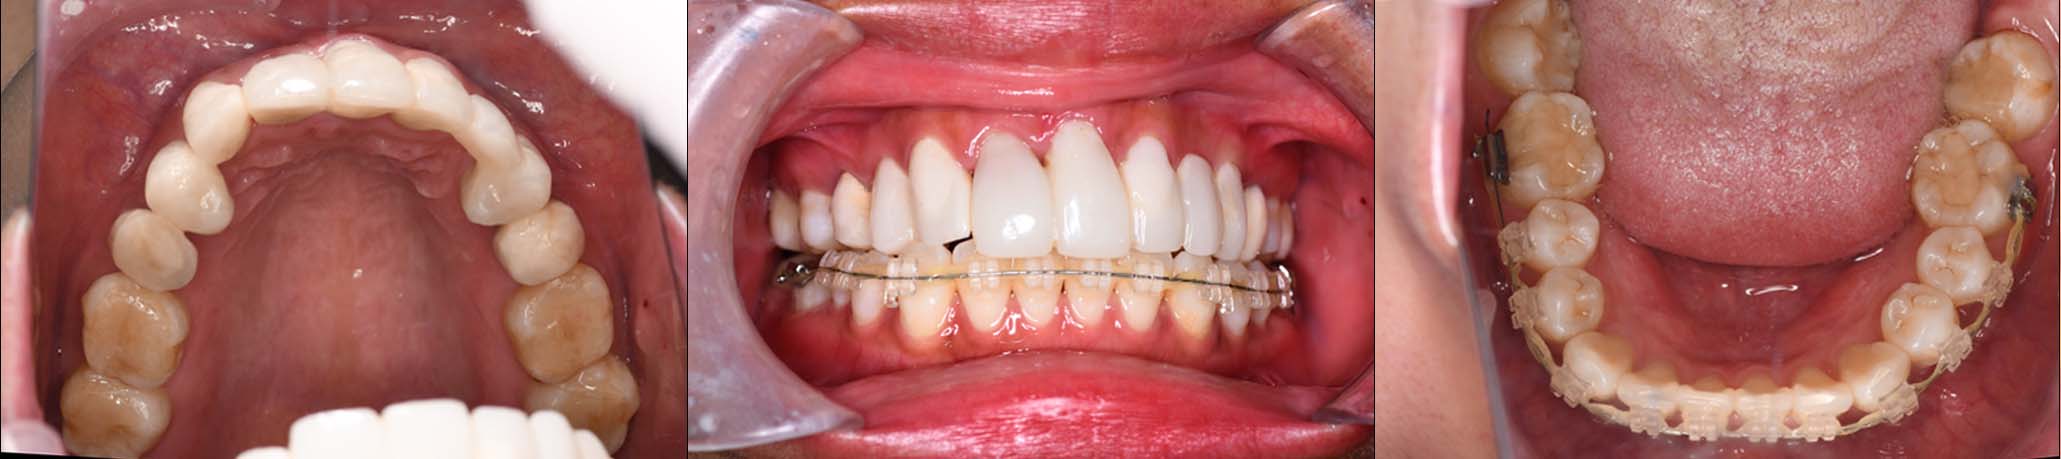

| 治療内容 | ①スプリントを装着 ②副子を装着 ③2024年4月 口腔内反映開始 ④副子を入れた状態の所まで咬合を挙上 (バイトアップ) ⑤2024年5月 上顎前歯部8本に仮歯(TEK) を装着 |

10月21日

11月7日

11月28日